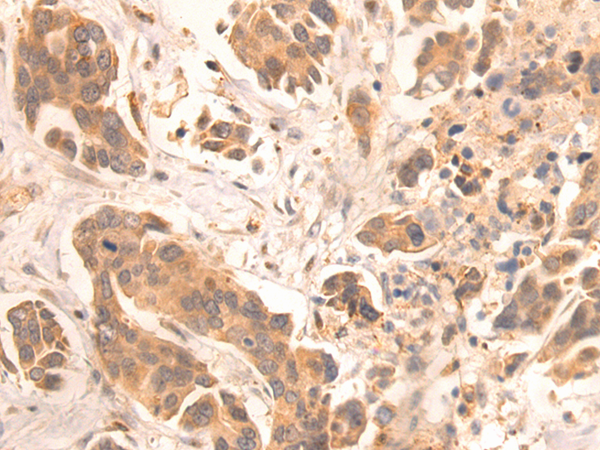

IHC positive control: |

Human gastric cancer |